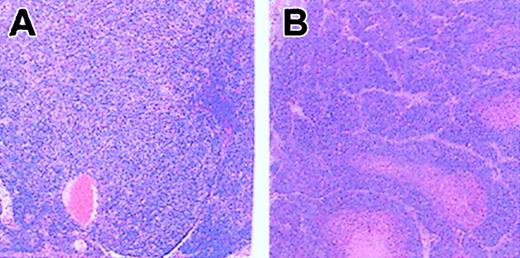

Hematoxylin and eosin–stained, paraffin-embedded tissue sections from old C57Bl/6 Fancc-/- mice. (A) Small intestine lymph node showing histiocytic sarcoma with sheets of neoplastic cells characterized by eosinophilic cytoplasm and pleomorphic nuclear morphology. (B) Mammary adenocarcinoma with well-circumscribed and encapsulated mass composed of neoplastic cells with oval or polyhedral nucleus with either amphophilic nuclei and stippling or coarse pattern to their chromatin. Anisokaryosis is 2-fold and mitotic index is 5. Original magnification × 100.

The first phenotype considered new in Fancd2-/- mice is microphthalmia. I and others2 have observed microphthalmia in Fancc and Fanca knock-out mice, respectively. For instance, microphthalmia was observed in 2 Fancc-/- mouse strains, C57Bl/6 and C57Bl/6Ly-Pep3b, at 63.5% (57 of 90) and 63.3% (54 of 85), respectively, compared with 78% (33 of 41) of Fancd2-/- mice. Like those of Houghtaling et al, my nonmutant C57Bl/6 mice showed a low incidence of microphthalmia (2% or 4 of 199). Since microphthalmia seems to be more frequent in a C57Bl/6 background and in view of the fact that the first FA mouse model reported3 has been done using mixed background (129sv/C57Bl/6j), this may explain why microphthalmia had not been previously observed. The second so-called novel phenotype is perinatal lethality. Houghtaling et al reported that only 16.5% (50 of 303) of Fancd2-/- mice were observed versus the expected 25% at the time of genotyping, suggestive of perinatal lethality. I observed a ratio of 19.6% (121 of 616) and 16.4% (132 of 804) in Fancc-/- mouse strains C57Bl/6 and C57Bl/6Ly-Pep3b, respectively, also indicating perinatal lethality. The third phenotype observed in Fancd2-/- mice that was suggested to be specific to this complementation group is the increased incidence of tumors. Again the authors believe that this occurrence is due to the complete loss of Fancd2 function, a function that is dependent on its monoubiquitination. However, Wong et al recently reported tumor formation (lymphoma) in 33% (2 of 6) of Fanca-/- mice from the 129S6:CD-1 background.2 We also observed tumors in older Fancc-/- mice (> 13 months of age; M.C., C. McKerlie, M. Buchwald, unpublished observation, May 2001). Unfortunately, we did only histologic analysis of 2 Fancc-/- C57Bl/6 mice, and in these 2 cases, tumors were observed; the first tumor was mammary adenocarcinoma (same as Fancd2-/- mice) and the second, histiocytic sarcoma (Figure 1). Since only 2 mice had been kept for a longer period of time, these results have not been reported before. Nevertheless, I believe that increased incidence of tumor formation in FA mouse models is not solely observable in the Fancd2 subgroup and is probably a phenotype directly linked to the FA pathway, that is, resulting from lack of a functional FA gene, any FA gene. Thus, Houghtaling et al's statement that Fancd2-/- mice have important differences to other FA mouse models is not accurate.